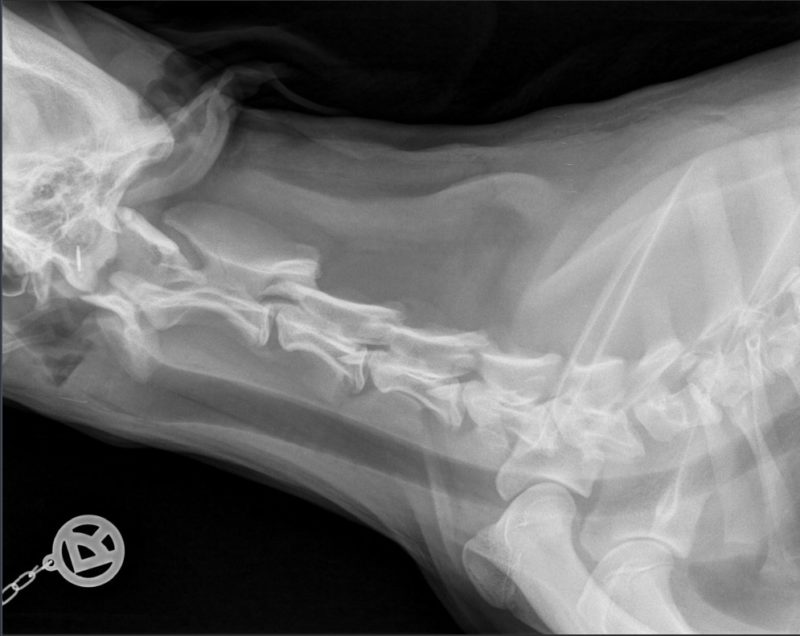

Um andere Ursachen für die Schmerzhaftigkeit auszuschließen, wurde bei Ronja ein Röntgenbild der Halswirbelsäule gemacht. Eine Möglichkeit für Schmerzhaftigkeit in der Halswirbelsäule kann auch eine Entzündung der Bandscheiben oder ein Bandscheibenvorfall sein. Dies konnte bei Ronja durch die röntgenologische Untersuchung ausgeschlossen werden.